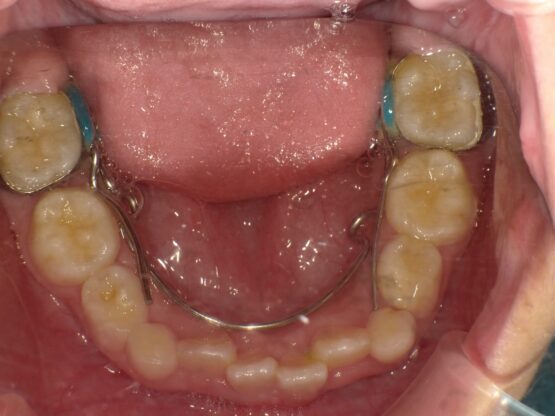

上顎の骨には繋ぎ目が存在しており、そこで左右二つの骨に分かれています。急速拡大装置を上顎に固定して装置の中央にあるネジを回すことで繋ぎ目を広げ、徐々に上顎の骨の変えていきます。そうすることで、顎の骨が正しい形に成長していくよう促され、永久歯を正しい位置で生えるように誘導できます。

急速拡大装置で上顎の拡大が進むと、下顎の骨も調整する必要が出てきます。その際に使う装置がリンガルアーチです。下顎の骨は上顎の骨と作りが違います。下顎はひとつの骨で構成されているので、上顎と同じように拡大させることができません。内側に傾いている歯を起こすようにして歯列部分だけを拡げていきます。この装置も固定式の装置となっており、歯の裏側に装着しますので目立たない見た目となっています。